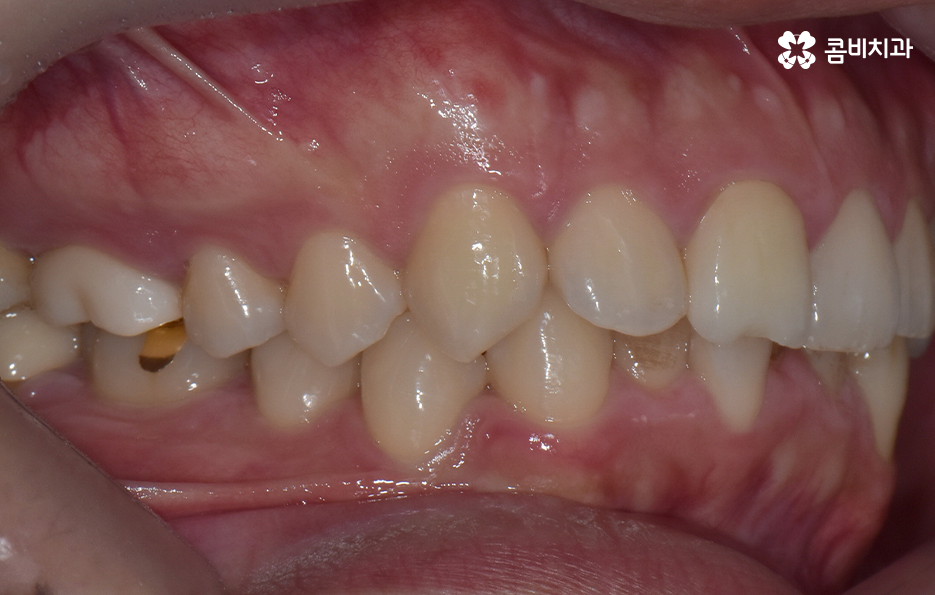

하지만 위에 보시는 환자분의 사례는 윗니와 아랫니의 교합을 고려하고 얼굴형, 골격 등을 고려했을 때도 아랫니만 교정이 가능했던 사례인데 일반적으로 윗니가 아랫니를 살짝 덮고 있어야 하는데 아랫니의 앞니 부분이 유독 안으로 들어와 있었기 때문에 아랫니교정 만으로도 치아교정이 가능했던 사례라고 보시면 좋을 거예요

위 환자분의 사례로 보면 아랫니 중에 하나가 유독 앞으로 튀어나와 있고 나머지 치아는 안으로 들어가 있기 때문에 교합으로 따져볼 때는 아랫니를 전체적으로 앞으로 이동시켜야 했기 때문에 비발치로도 충분히 교정이 가능했고 아랫니교정 만으로도 치료가 가능했어요